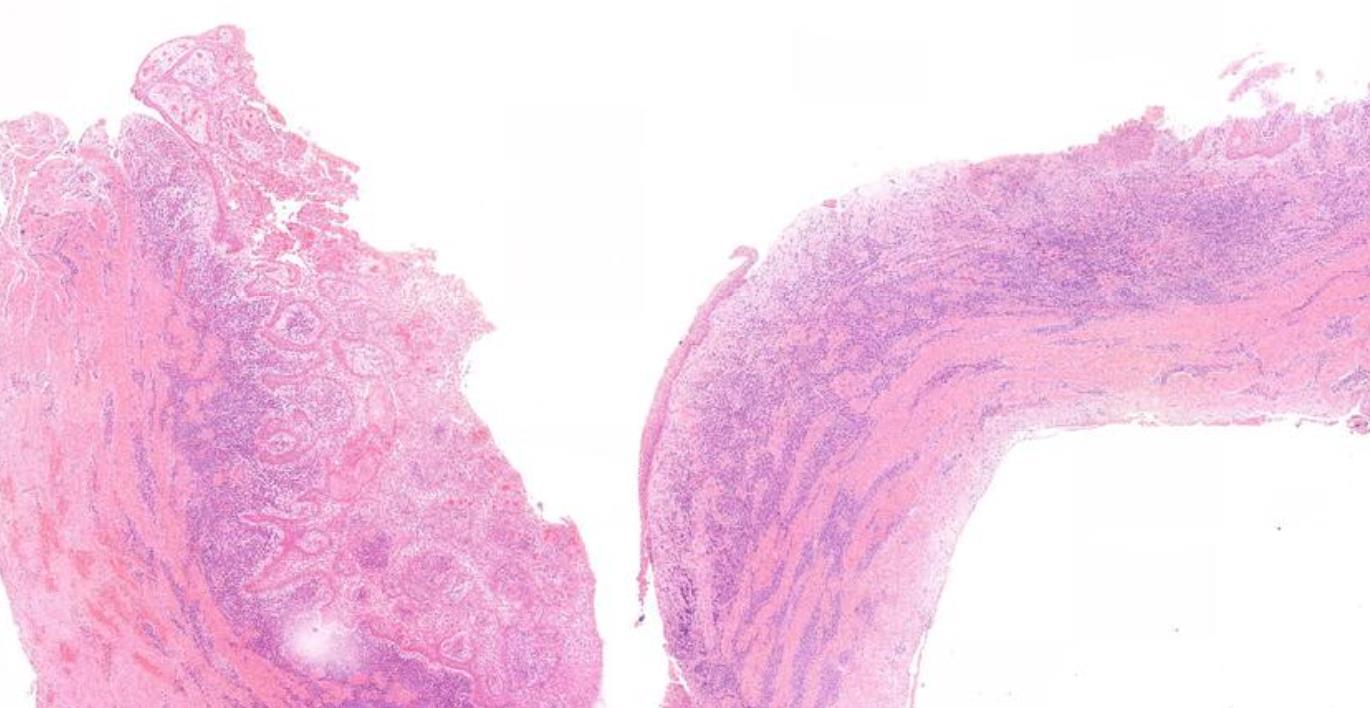

Case 5- Salient points • Non-specific thin squamous epithelial lined cyst • No keratinisation, basal palisading • Largely uninflamed fibrous cyst wall • Location + histology

??

Case 5 Diagnosis

Dentigerous cyst